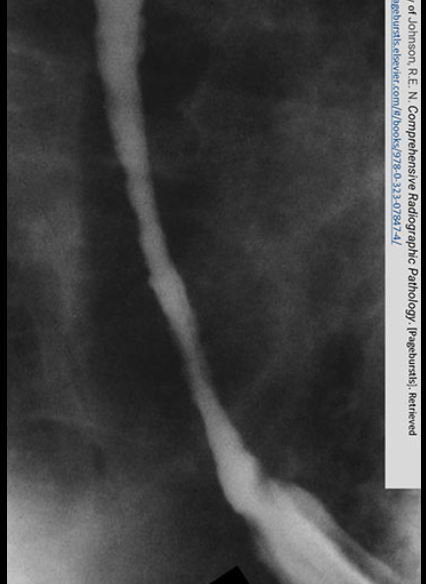

advanced stage of GERD

Obvious narrowing of the lower esophagus due to reflux. Notice the erosion.